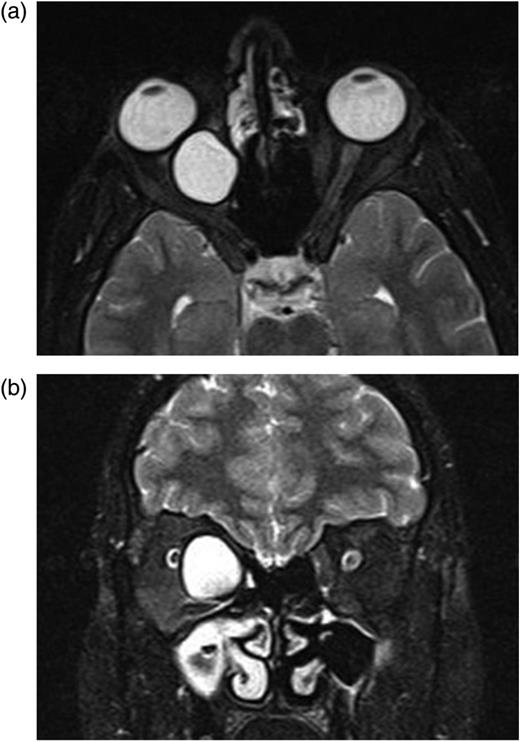

A complete blood cell count and serum laboratory values were normal without mild eosinophilia. Axial-coronal orbital magnetic resonance imaging (MRI) revealed a well-defined homogenous unilocular lesion in intraconal region of the right orbita which was hypointense on T1-weighted images and hyperintense on T2-weighted images after an intravenous injection of gadolinium-ethoxybenzyl-diethylenetriamine pentaacetic acid (Fig. 2a and b). The lesion was adjacent to optic nerve and medial rectus muscle and exerting pressure on the optic nerve and displacing optic nerve laterally. Approximate dimension of the lesion was 2 cm × 2 cm × 2 cm (Fig. 2a and b). Because it was difficult to distinguish hydatid cyst from other mass lesions of the orbita via MR, other mass lesions like neurocysticercosis, dermoid, lipodermoid, mucocele, encephalocele, inclusion cyst, teratoma, hematocele, schwannoma and paraganglioma were considered in the differential diagnosis of hydatid cyst.

(a and b) Axial-coronal orbital magnetic resonance imaging show the homogenous unilocular lesion that is adjacent to optic nerve and medial rectus muscle in the intraconal space and displacing optic nerve laterally.